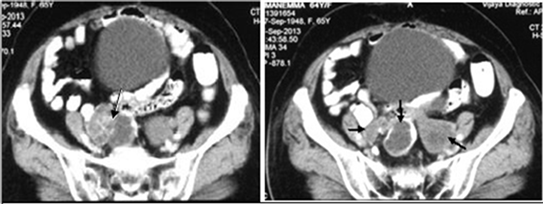

Figure 8. Recurrent hydatidosis pelvis in a 64 yr female patient with history of salphingo-oophorectomy for ovarian hydatid cysts. CECT abdomen showed multiple cysts at various stages. Class CE1 cyst is iso dense with peripheral high attenuation rim, class CE2 cyst filled with multiple vesicular cysts with ”spoke wheel” appearance with high attenuation wall and internal septa, another CE5 cyst with thick peripheral calcifications.

Figure 9. Complicated class CE3 hydatid cyst in right lung in a 69 yr old female patient with history of cough with expectoration, Plain CT chest revealed thin walled, air filled cavity with twisted membranes within, with ”spin/whirl” appearance.

Type IIC lesions appear as relatively high attenuation round or oval masses with scattered calcifications and occasional daughter cysts. These findings represent degeneration of old cysts with amorphous and tenacious content [Figure 7 and Figure 8].

Complicated cysts: Complications include rupture and superinfection and may be seen in type I and type II. Cyst rupture is mainly due to degeneration of parasitic membranes, risk of rupture increases with the size, anthelminthic therapy and percutaneous aspiration [7] . Cyst rupture may be contained, communicating, or direct. In contained rupture, the endocyst ruptures and the cyst contents are confined within the pericyst [Figure 2, Figure 9, Figure 12]. In communicating rupture, the cyst ruptures into the biliary and bronchial radicles lying in the pericyst, rarely into vascular system, such as portal vein, IVC, pulmonary artery, rare but cyst rupture into IVC and right sided cardiac chambers present as recurrent cystic pulmonary embolism. They may or may not be infected [5] . Indirect signs of communicating rupture are deformity of cyst, defect in the wall, presence of beak like projection extending from cyst wall, dilated bile ducts and daughter vesicles or germinative membranes of cysts in bile ducts on MRCP/ERCP, presence of fat inside the cysts on CT/MRI in cysts with biliary tree communication [Figure 14]. Direct sign is visible communication but is difficult to demonstrate with imaging due to high intra cystic pressure than bile ducts. [2] [3] [5] [6] [7] [8] . Rupture into the bronchus is the most frequent complication of pulmonary hydatid disease, produces an allergic pneumonitis in the surrounding areas. This is reversible up to 10days and after 10 - 14 days secondary bacterial pneumonia develops. In direct rupture, both the endocyst and the pericyst rupture, with spillage of cyst contents into the peritoneal, pleural cavities or other structures, rarely into a hallow viscus, such as stomach or colon, into ventricular system, subarachnoid spaces, pcs. Direct rupture has the greatest clinical consequences including anaphylaxis, hydatid dissemination, secondary bacterial infection, and recurrences after surgery. Peripherally located cysts are more prone to direct rupture due to deficient pericyst and little host tissue support [3] [5] [7] . Indirect signs of infection are gas/air fluid levels [Figure 9, Figure 11, Figure 12].